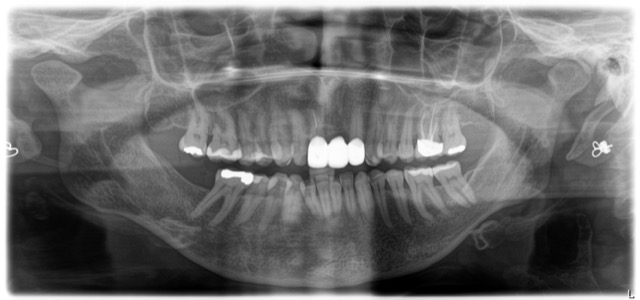

in oktober 2022 heb ik een nieuwe brug laten plaatsen vanwege doorschijnen van het metalen fundament van de 15 jaar oude brug.

Nadat de nieuwe brug is geplaatst ( keramisch fundament), verscheen er een zwart randje tussen de brug/tandvlees en de onderliggende pijler.

De tandarts heeft de onderliggende pijler gebleekt, dat was verholpen.

Alleen na verloop van tijd is het zwarte randje weer.. Ben door mijn tandarts verwezen naar een Paradontoloog voor tandvleestransplantatie. De paradontoloog vond dit geen mogelijke oplossing.

Het zwarte randje is van de bestaande tand, deze heeft in het geleden al een wortelkanaal behandeling gehad. Tandvlees transplantatie is niet mogelijk om dat het tandvlees weer zal optrekken ( gevoelig). Paradontoloog wil mijn gebit herstellen, zodat mijn kiezen weer normaal op elkaar staan. Ik klem en knars ook…, waardoor brug er niet beter op zal worden en in de loop van de tijd meer naar voren komt te staan..